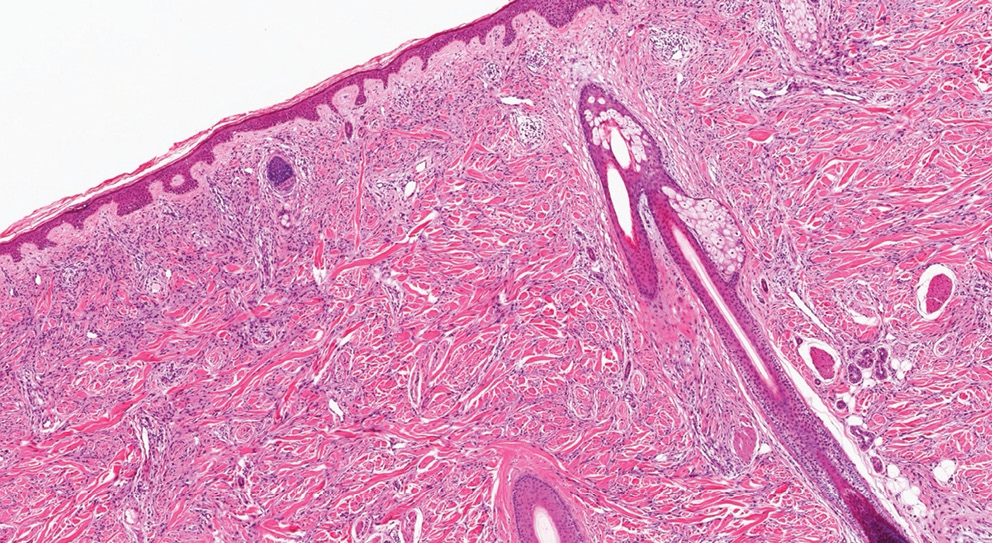

Дерматологический статус. На коже спины в подлопаточной области определяется узел диаметром 2 см с гиперпигментацией, фиброзной плотностью и линейными сосудами (рис. 3). Кожа вокруг без признаков воспаления, локальной гиперемии нет.

Рис. 3. Десмопластическая меланома (микроскопическое исследование, × 100, окрашивание гематоксилином и эозином). Разнонаправленные пучки базофильных опухолевых клеток в толще сосочков ретикулярной дермы

Fig. 3. Desmoplastic melanoma (microscopic examination, ×100, H&E staining). Multidirectional bundles of basophilic tumor cells within the papillary layer of the reticular dermis

Инструментальные методы исследования. При дерматоскопии выявлены атипичная сосудистая сеть, отсутствие четких границ и участки белесоватой стромы. Гистологический анализ подтвердил плотную коллагенизированную структуру опухоли с нейротропной инвазией. Иммуногистохимическое исследование выявило выраженную экспрессию S100 и SOX-10.